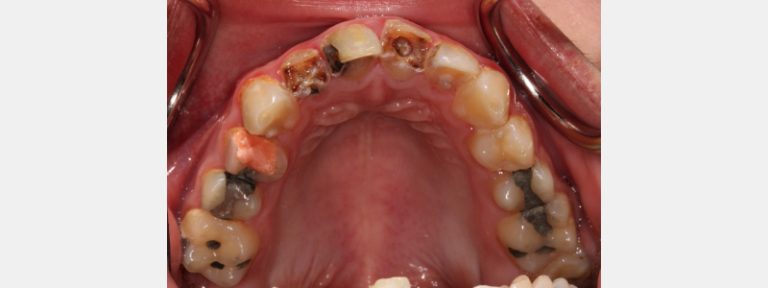

Caries detection dyes help dentists determine when to stop tooth preparations in conservative treatment.